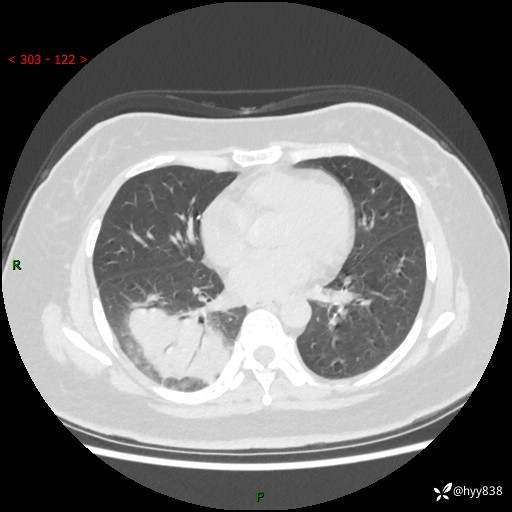

大叶性肺炎的表现形式,晒晒鉴别诊断吧…结果公布~

简要病史:患者8天前无明显诱因出现咳嗽、咳痰,为绿色脓痰,无明显加重与缓解因素,无高热、寒战,无呼吸困难,无大量脓痰,无哮鸣音,于当地医院行胸片示右下肺团块影,性质待定,予口服药物治疗症状未见明显改善,具体药名不详,为求进一步诊治来我院就诊,门诊以“肺占位性病变”收入我科进一步诊治。 患者自发病以来,精神、饮食尚可,睡眠欠佳,大小便正常,体力、体重未见明显异常。

辅助检查:CT

胸部CT平扫